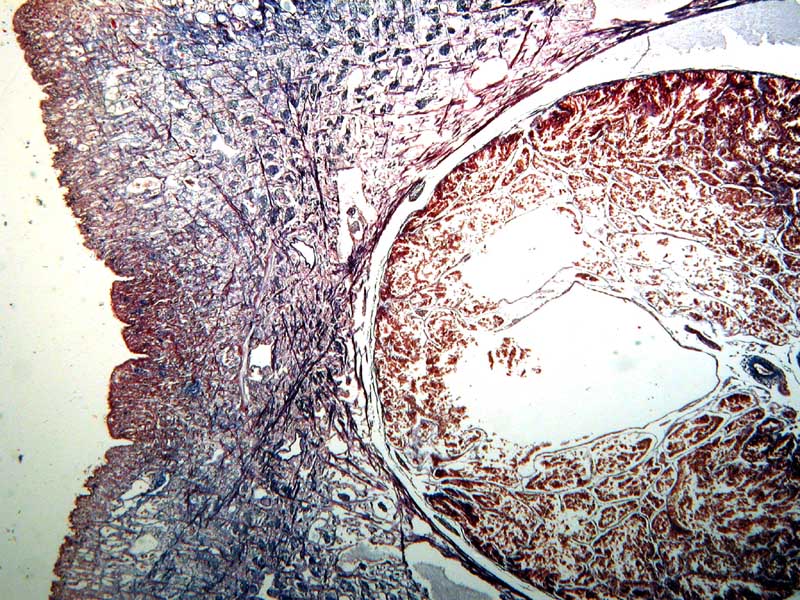

Mikroskopische Präparate

An anderer Stelle dieser Homepage

habe ich

Übersichtsbilder mikroskopischer Präparate vorgestellt, die mit einem

einfachen Makrokonverter aufgenommen wurden. Nachfolgend sehen Sie Bilder

derselben Präparate, aufgenommen mit dem Photomakroskop: